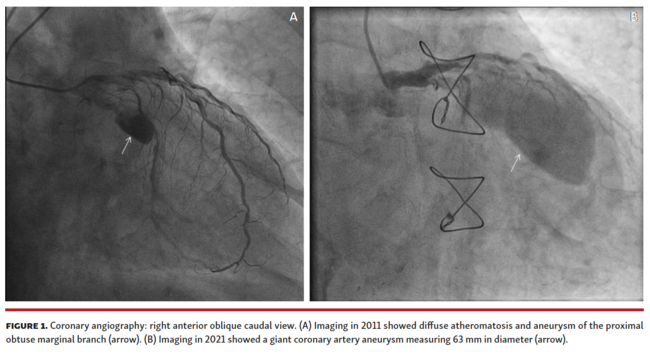

A 78-year-old man with chronic atrial fibrillation, diabetes mellitus, and prior coronary artery bypass grafting (CABG) was admitted for coronary angiography due to severe aortic valve stenosis. A known coronary artery aneurysm (CAA) in the obtuse marginal (OM) branch was an incidental finding on a coronary angiography performed 10 years ago, just prior to the CABG operation (Figure 1A).

The current coronary angiography depicted a giant CAA of the OM as a result of progressive size growth during this 11-year period (Figure 1B; Video 1). On computed tomography coronary angiography (CTCA), the CAA measured 63 mm in diameter and contained intraluminal thrombus (Figure 2A). The patient was referred for aortic valve replacement and aneurysm resection; however, the aneurysm was deemed to be non-resectable due to severe calcification, thus posing a high operative risk. The patient eventually underwent transcatheter aortic valve implantation.